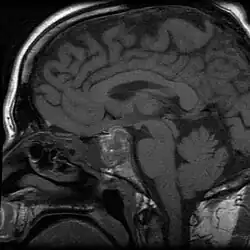

Apoplexy (from Ancient Greek ἀποπληξία (apoplexia) 'a striking away') refers to the rupture of an internal organ and the associated symptoms. Informally or metaphorically, the term apoplexy is associated with being furious, especially as "apoplectic". Historically, it described what is now known as a hemorrhagic stroke, typically involving a ruptured blood vessel in the brain; modern medicine typically specifies the anatomical location of the bleeding, such as cerebral apoplexy, ovarian apoplexy, or pituitary apoplexy.[1][2][3]

To specify the site of bleeding, the term "apoplexy" is often accompanied by a descriptive adjective. For instance, bleeding within the pituitary gland is termed "pituitary apoplexy", and bleeding within the adrenal glands is referred to as "adrenal apoplexy".[9]

Apoplexy also includes hemorrhaging within the gland and accompanying neurological problems, such as confusion, headache, and impairment of consciousness.[10]